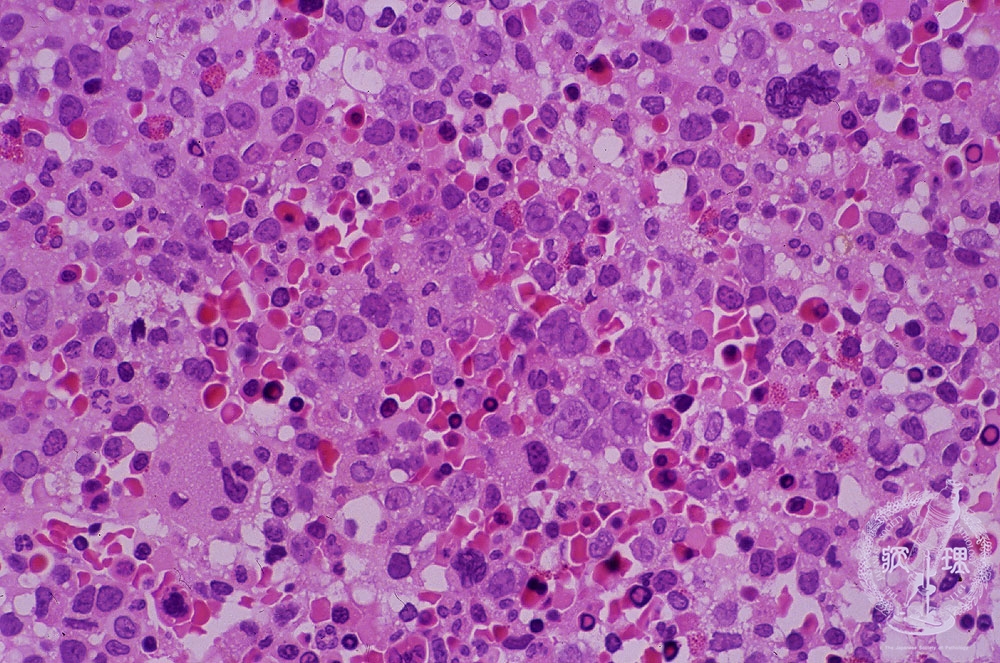

- 1.Bone marrow / Hematopoietic system

- (2)Megaloblastic anemia

Microscopic image (H&E high power view): Although an anemia is found in the peripheral blood, bone marrow shows marked hypercellularity with increased erythroblasts forming small aggregates. Megaloblasts have a relatively fine chromatin and the marked nucleoli (arrows). This type of anemia occurs due to the exhaustion of Vitamin B12 or folic acid by insufficient intake, malabsorption and/or excessive consumption.

Click the image to see the enlarged image.